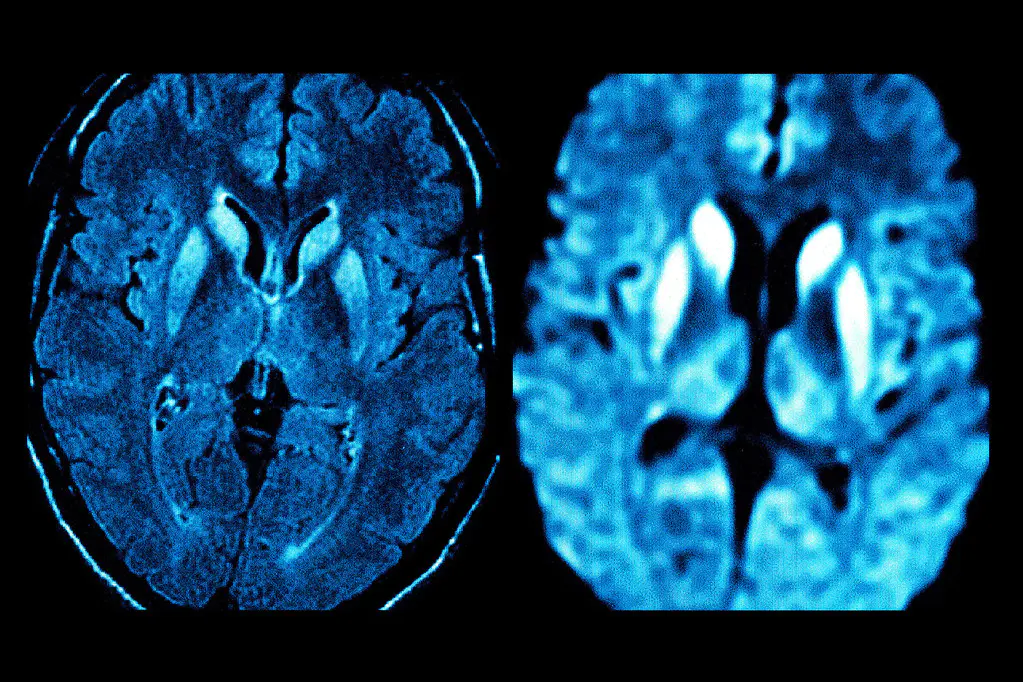

视神经脊髓炎的病灶不仅仅局限在视神经、脊髓两个部位。视神经脊髓炎是多发性的,而且患病时间越长,出现亚临床病灶的机会越多。早期发现这些脑部隐匿性病灶,提示临床及时对症治疗,可有效地减轻视神经脊髓炎致残的不良后果。